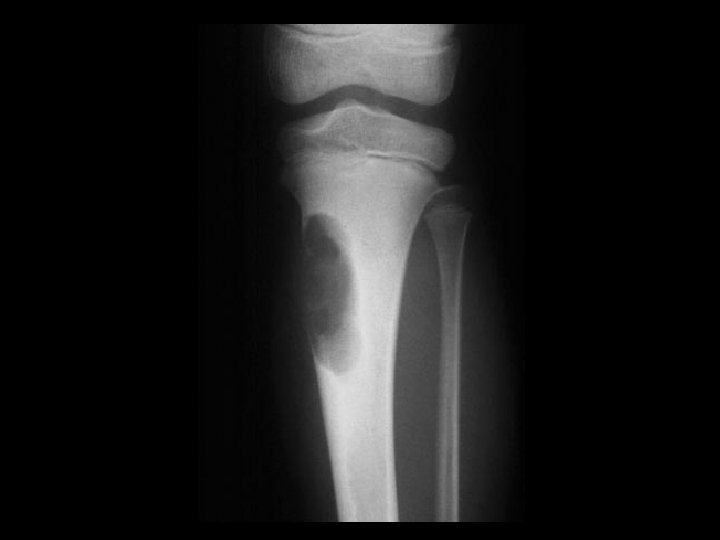

Aneurysmal bone cyst Findings Eccentric metadiaphyseal lucent lesion

Aneurysmal bone cyst • Findings: – Eccentric metadiaphyseal lucent lesion with a thin sclerotic margin and fine internal septa • ddx: – Fibrous dysplasia – Chondromyxoid fibroma – GCT, chondroblastoma (if physis closed)